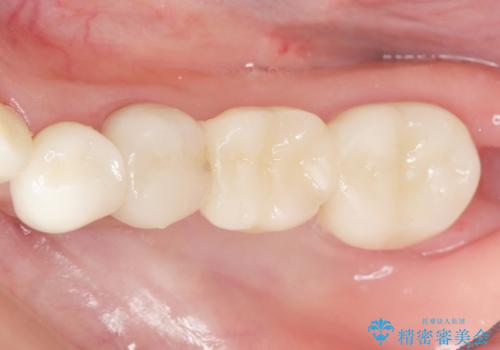

ブリッジに見えない自然な仕上がりに喜んでいただくことができました。